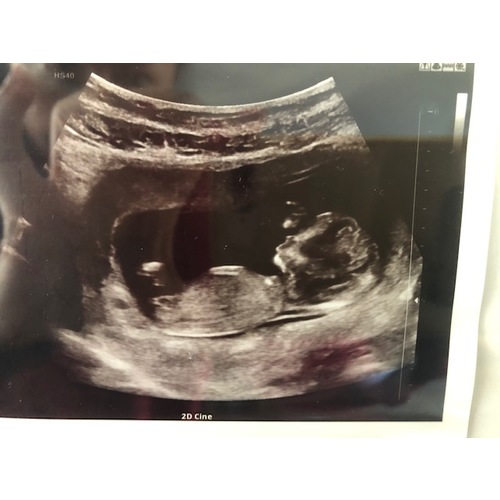

Wie durft een gokje te wagen? Ik ben benieuwd :)

Echo is van 12+4 dagen. Over 4 weekjes weet ik het!

Liefs

Meisje